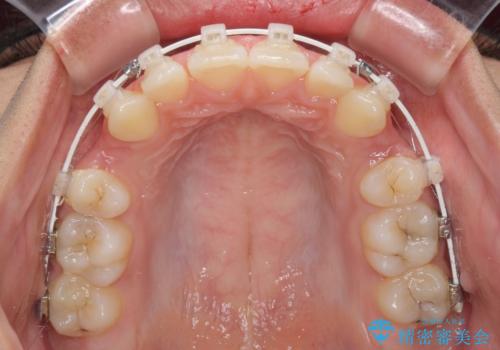

- 上下の出っ歯を気にして来院された患者様です。

口元を積極的に引っ込めるために、上下左右の第一小臼歯を4本抜歯することとしました。

前歯部の突出と開咬は、舌突出癖によるものでしたので、舌のトレーニングをしっかりと行っていただき、1年半程度と短期間で治療を終えることができました。